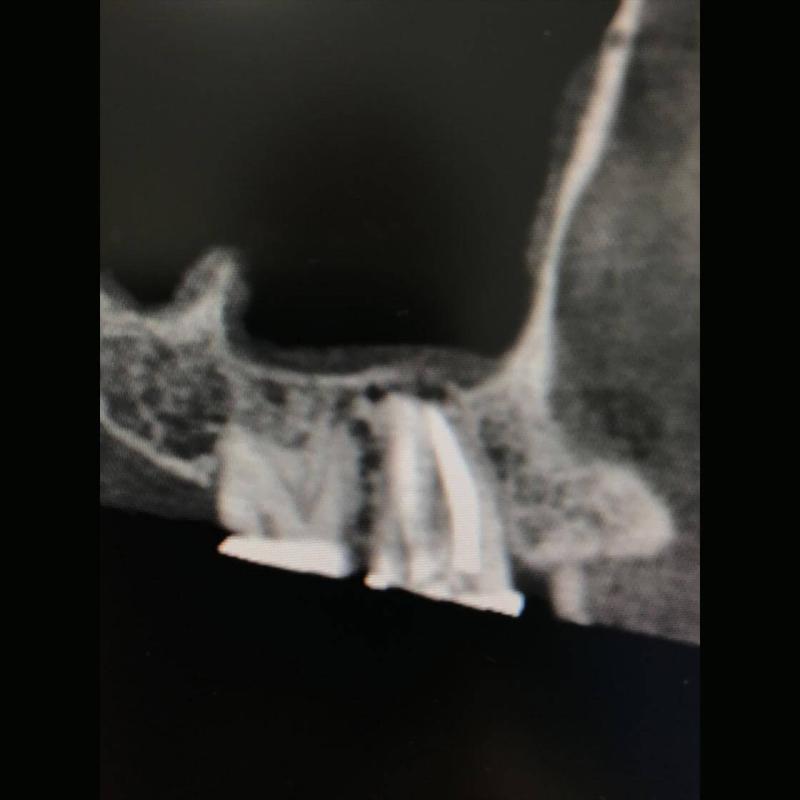

Lo Studio Zambon dispone di apparecchiature di ultima generazione, anche in campo diagnostico, come la Tac 3D Cone Beam, utilizzata in chirurgia, endodonzia e parodontologia, che consente una visione in 3D della struttura ossea e garantisce dosi radianti ridotte.